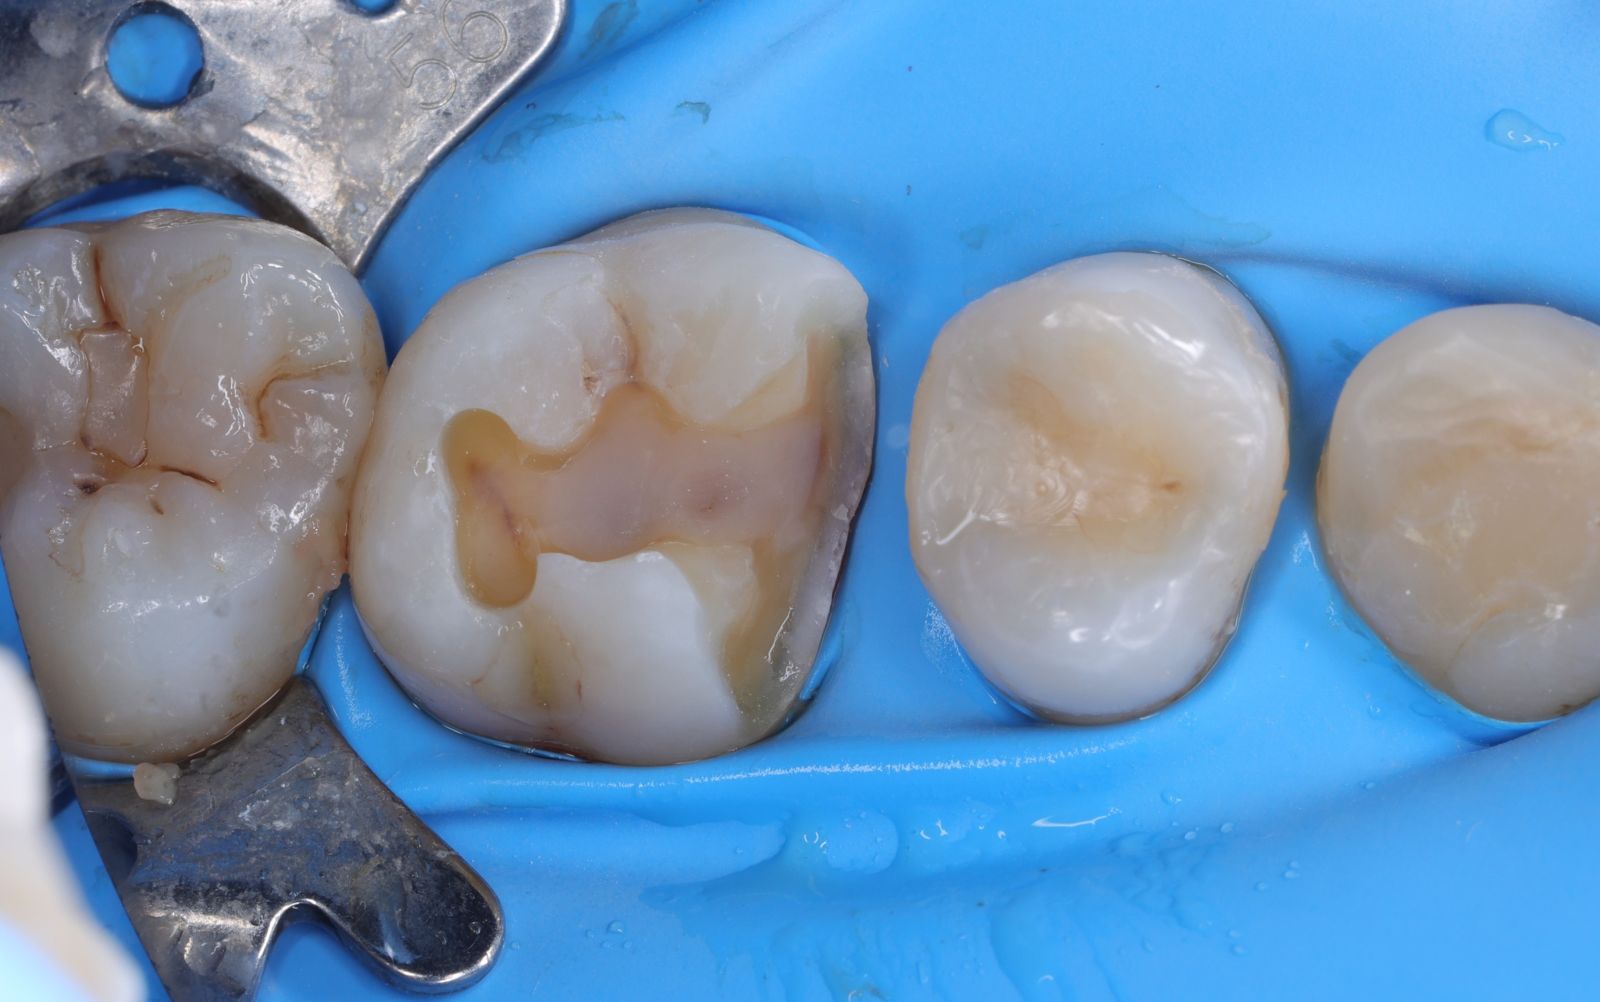

【 案 例 一 】

- 以前大範圍的樹脂補牙,久了造成二次蛀牙,不只是材料不密合,原本的牙齒還可能斷裂。把蛀牙挖乾淨後,隔絕感染源再印模,待陶瓷齒雕送回後再以特殊黏膠黏著完成!經過全陶瓷齒雕修復後,跟原先相比之下,牙齒恢復外型以外還能增強牙齒強度。